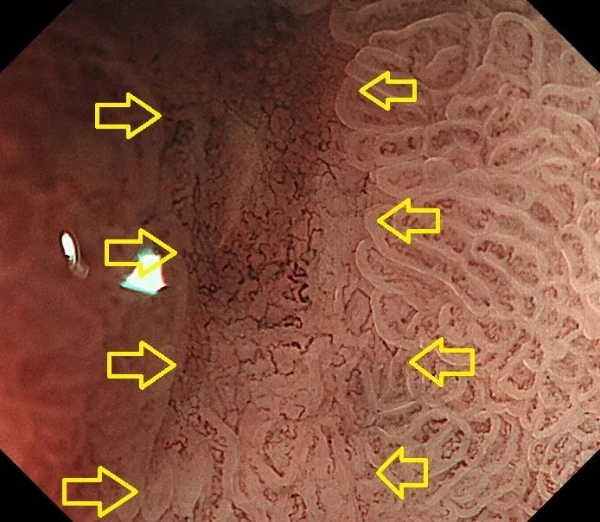

精查胃镜,简单来说,就是普通胃镜的升级版。是采用能放大80-100倍的放大胃镜、采用电子染色技术、4K超清成像技术等多种方法,发现肉眼无法发现的早期胃癌的一种早癌筛查技术。

精查胃镜,需要对胃黏膜色泽改变(如色泽斑驳不均的萎缩性胃炎)、微小的高低不平区域进行地毯式搜查,对可疑的病变采用电子染色技术(如第三代NBI染色技术)将可疑病变与周围正常区域区分开,然后对病变部位放大80-100倍,从而有效分辨出早期癌变。然后在此基础上进行精准靶向活检,可有效确认早期癌变。

(采用NBI染色+放大100倍观察,发现早癌)